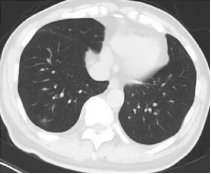

胸部CT:可见气道壁增厚、管腔轻度狭窄、气道壁少量渗出,存在中心性支气管扩张征象及双肺散在磨玻璃样浸润影。